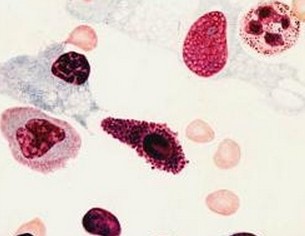

知名血液病医生葛林阜指出:血小板低是指血小板数低于正常范围所引起的病症。并且患者已经出现了典型的血小板减少症的症状,需要及时治疗,由于现在市场上的治疗方法越来越多,患者一定找到合适的治疗方法,才能***此病。